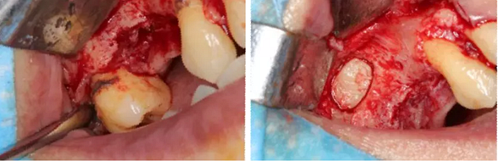

術(shù)后當(dāng)天 術(shù)后7個月

術(shù)后8個月 術(shù)后10個月